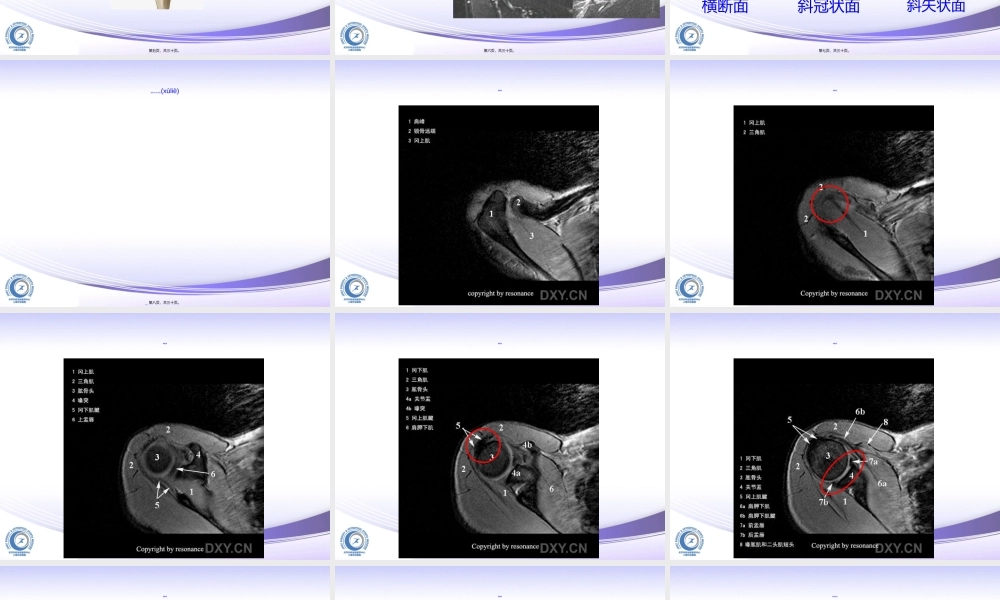

肩关节MRI读片2016.03.14第一页,共三十页。肩关节MRI肩袖关节(guānjié)盂、盂唇肌腱韧带滑囊骨病第二页,共三十页。肩袖第三页,共三十页。盂唇第四页,共三十页。肌腱(jījiàn)韧带第五页,共三十页。滑囊肩峰下-三角肌下滑囊肩胛(jiānjiǎ)下肌腱下滑囊喙突下滑囊第六页,共三十页。肩关节MRI扫描(sǎomiáo)横断面斜冠状面斜矢状面第七页,共三十页。肩关节MRI序列(xùliè)(jiégòu)第八页,共三十页。横断面第九页,共三十页。横断面第十页,共三十页。横断面第十一页,共三十页。横断面第十二页,共三十页。横断面第十三页,共三十页。横断面第十四页,共三十页。横断面第十五页,共三十页。斜冠状位第十六页,共三十页。斜冠状位第十七页,共三十页。斜冠状位第十八页,共三十页。斜冠状位第十九页,共三十页。斜冠状位第二十页,共三十页。斜冠状位第二十一页,共三十页。斜冠状位第二十二页,共三十页。斜矢状位第二十三页,共三十页。斜矢状位第二十四页,共三十页。斜矢状位第二十五页,共三十页。斜矢状位第二十六页,共三十页。斜矢状位第二十七页,共三十页。斜矢状位第二十八页,共三十页。谢谢(xièxie)第二十九页,共三十页。内容(nèiróng)总结肩关节MRI读片。谢谢(xièxie)第三十页,共三十页。